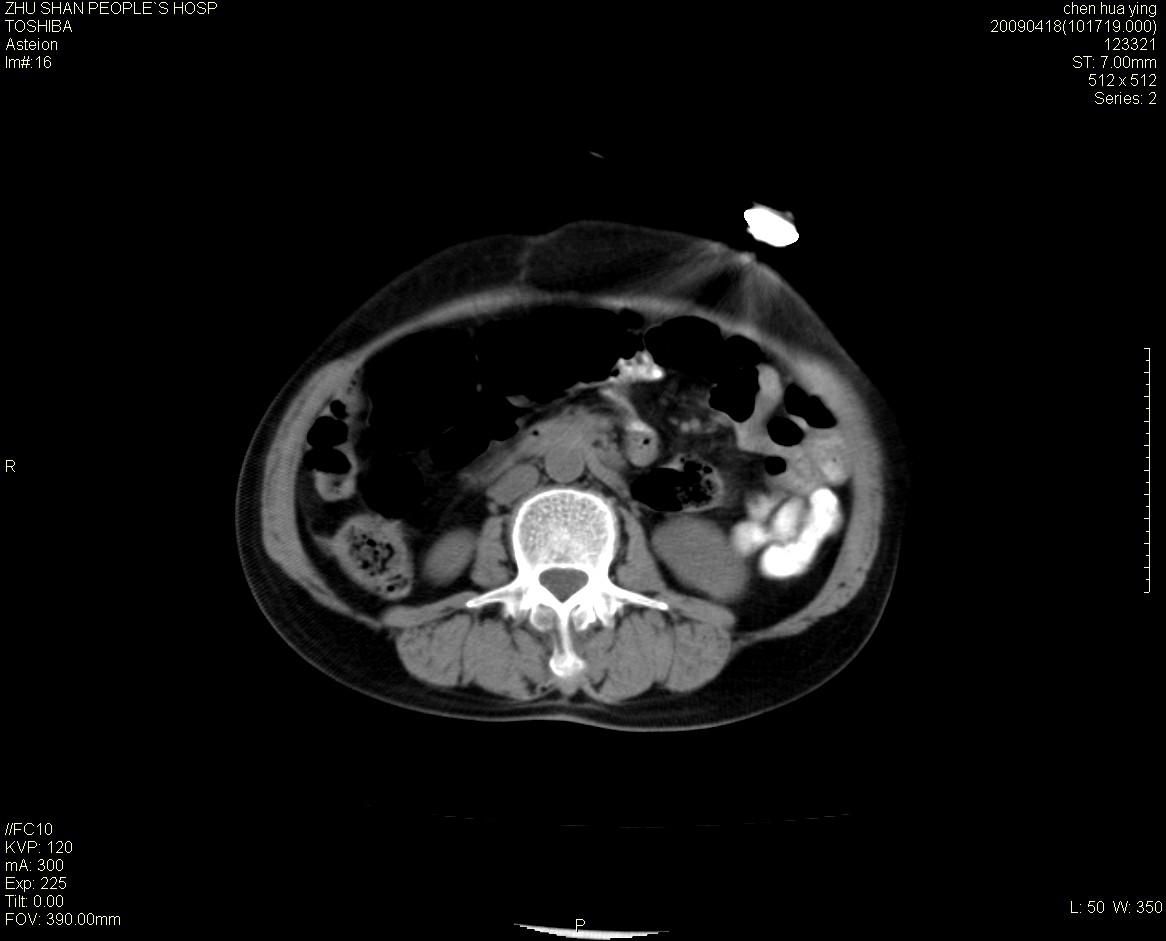

女性病人 65岁 腹部包块半年余结肠造影未见异常.

病灶略呈圆形有分叶状,上部层面呈实性,右侧见圆形低密度区,灶内见团块状钙化,病灶下方与肠管分境不清,考虑间质瘤可能性大,建议肠道准备后增强